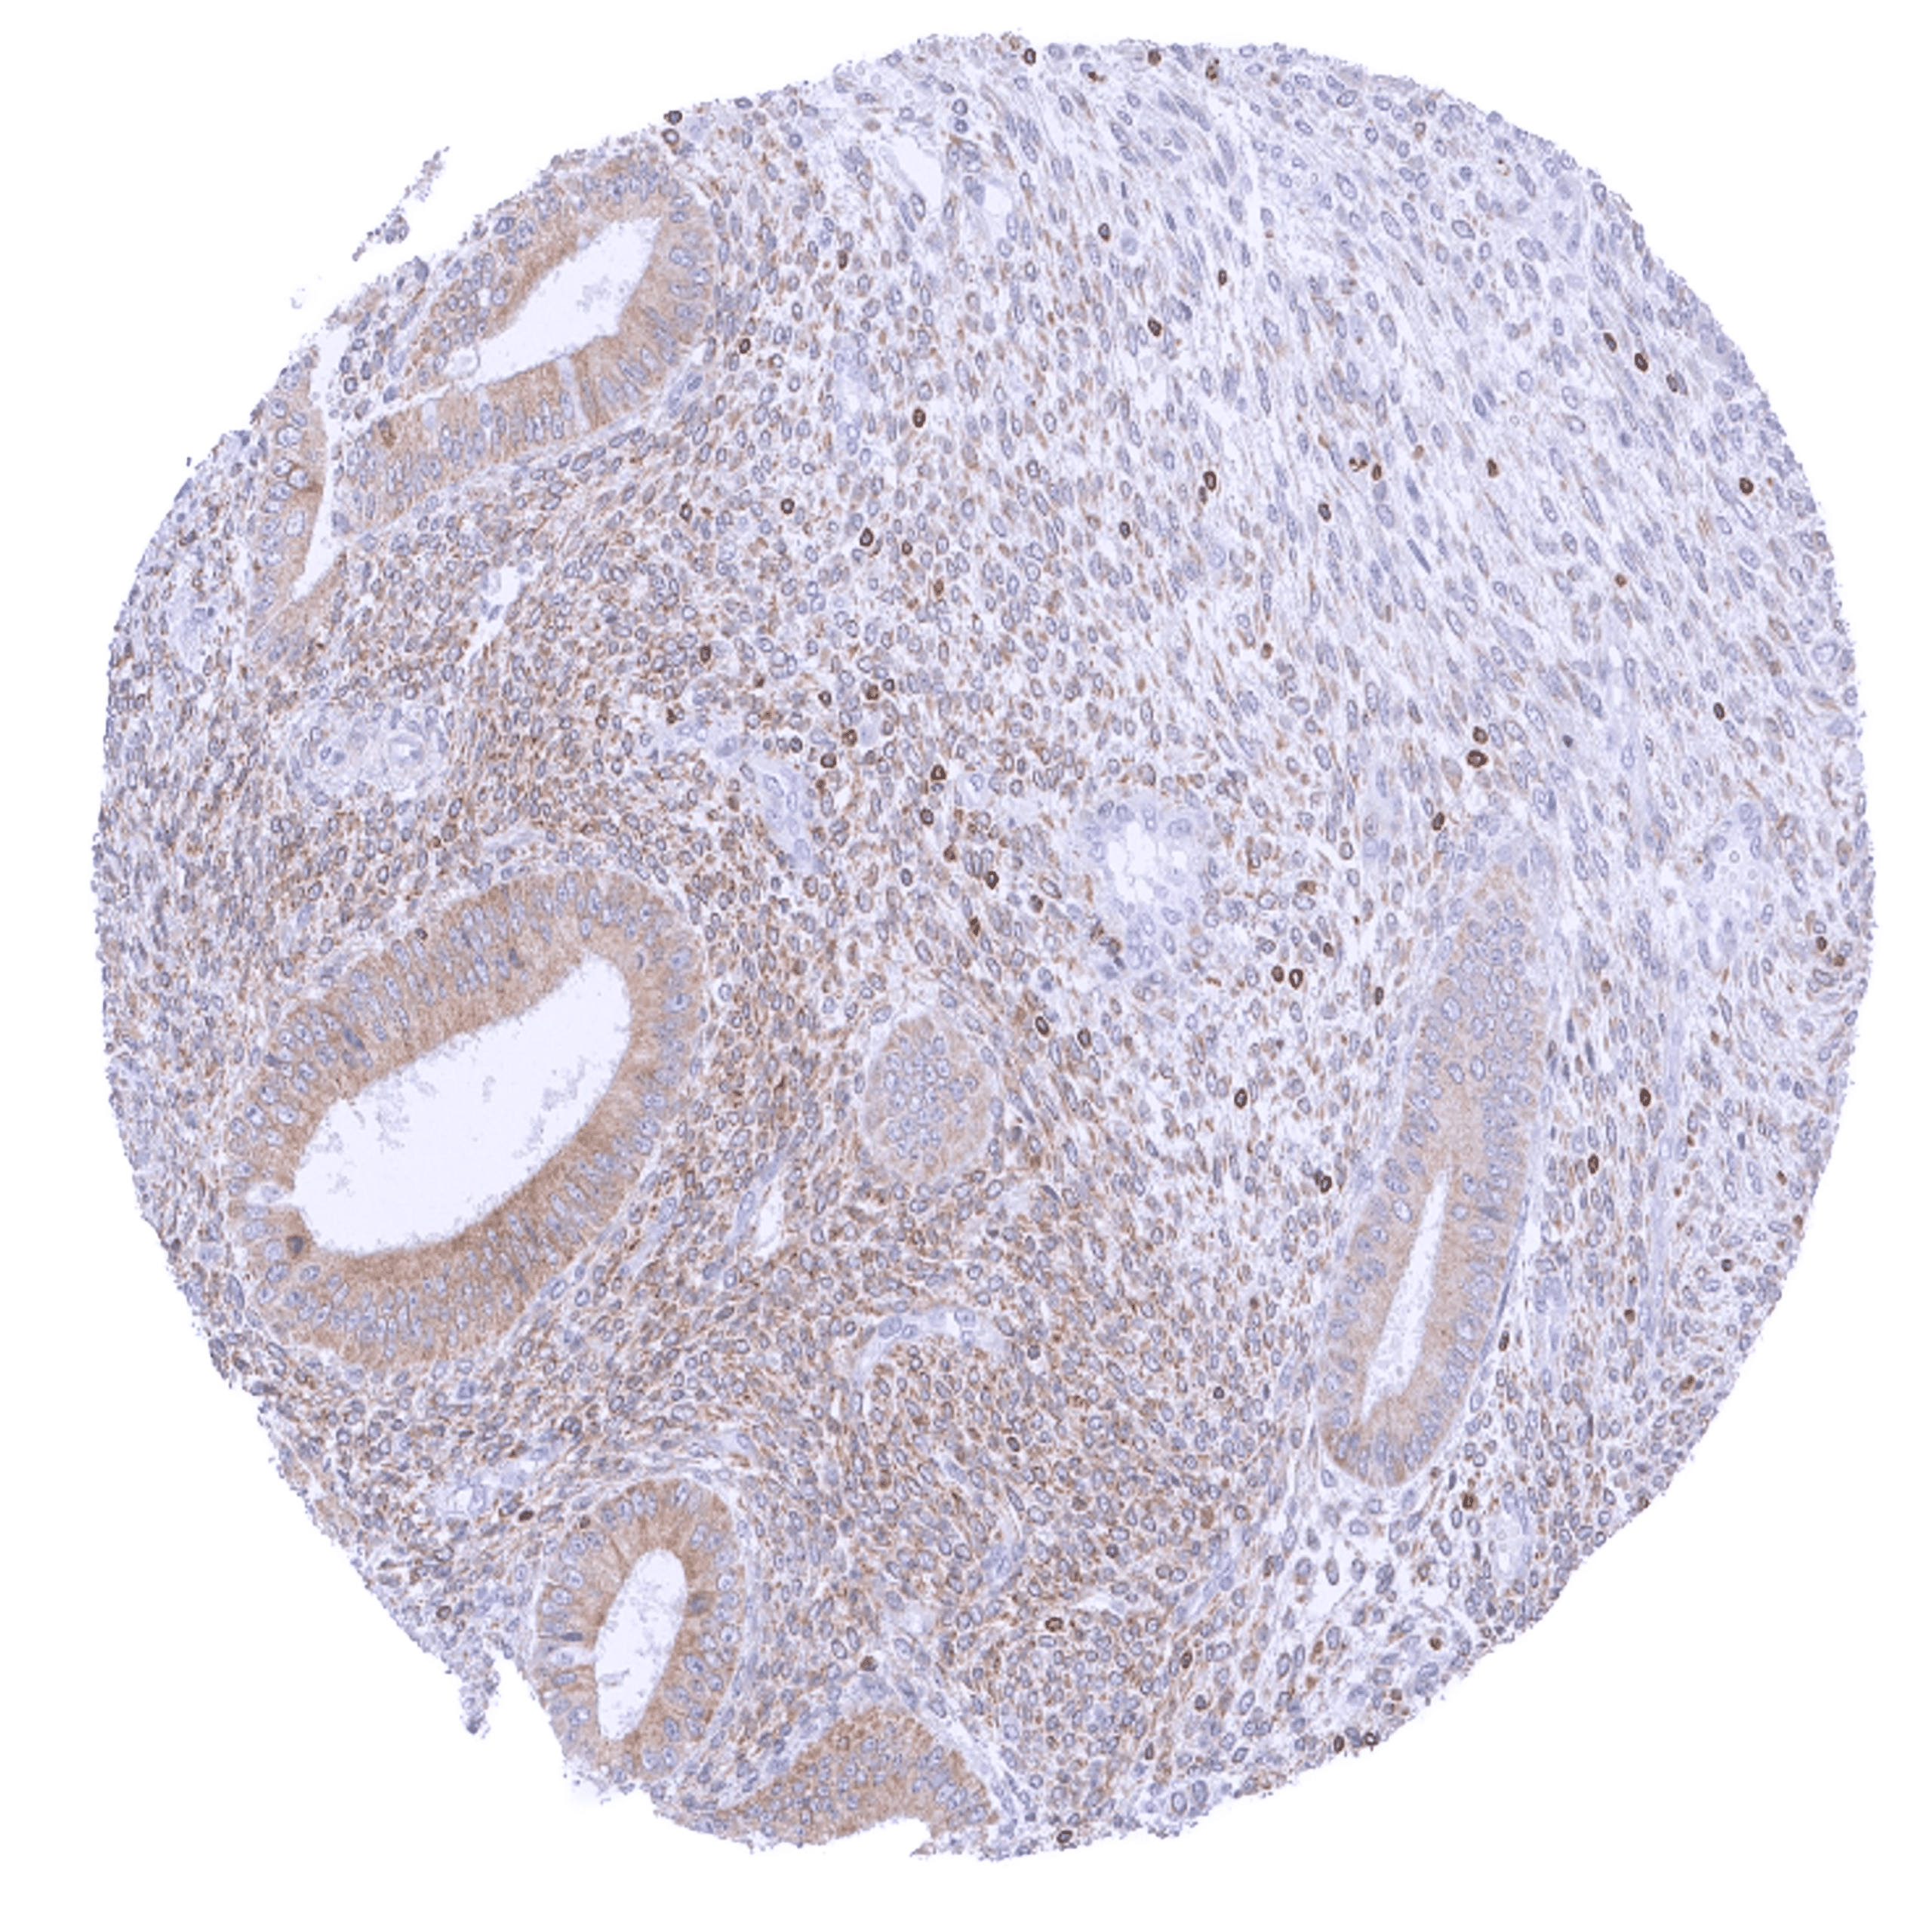

| Lymph node | Strong bcl-2 positivity of a large fraction of lymphocytic cells in the interfollicular area and around germinal centres while almost all cells in germinal centres are bcl-2 negative. | |

| Spleen | Strong bcl-2 positivity of the lymphocytes of the white pulpa and of a small fraction of cells in the red pulpa. | |

| Thymus | Strong bcl-2 positivity of a large fraction of lymphocytic cells in the medulla while corpuscles of Hassall’s are negative. Bcl-2 staining is less intense, variable, and often negative in lymphocytic cells of the cortex. | |

| Tonsil | Strong bcl-2 positivity of a large fraction of lymphocytic cells in the interfollicular area and around germinal centres while almost all cells in germinal centres are bcl-2 negative. Squamous epithelium is bcl-2 negative although the basal cell layer may show weak positivity. | |

Bcl-2 expression of variable intensity can occur in all types of cancer. It is particularly common in follicular lymphoma.

Comparison of antibodies: True expression of bcl-2 in all cell types with documented bcl-2 immunostaining by MSVA-402M is validated by identical staining patterns obtained by a second, independent commercially available bcl-2 antibody, termed “validation antibody” for all analyzed tissues.